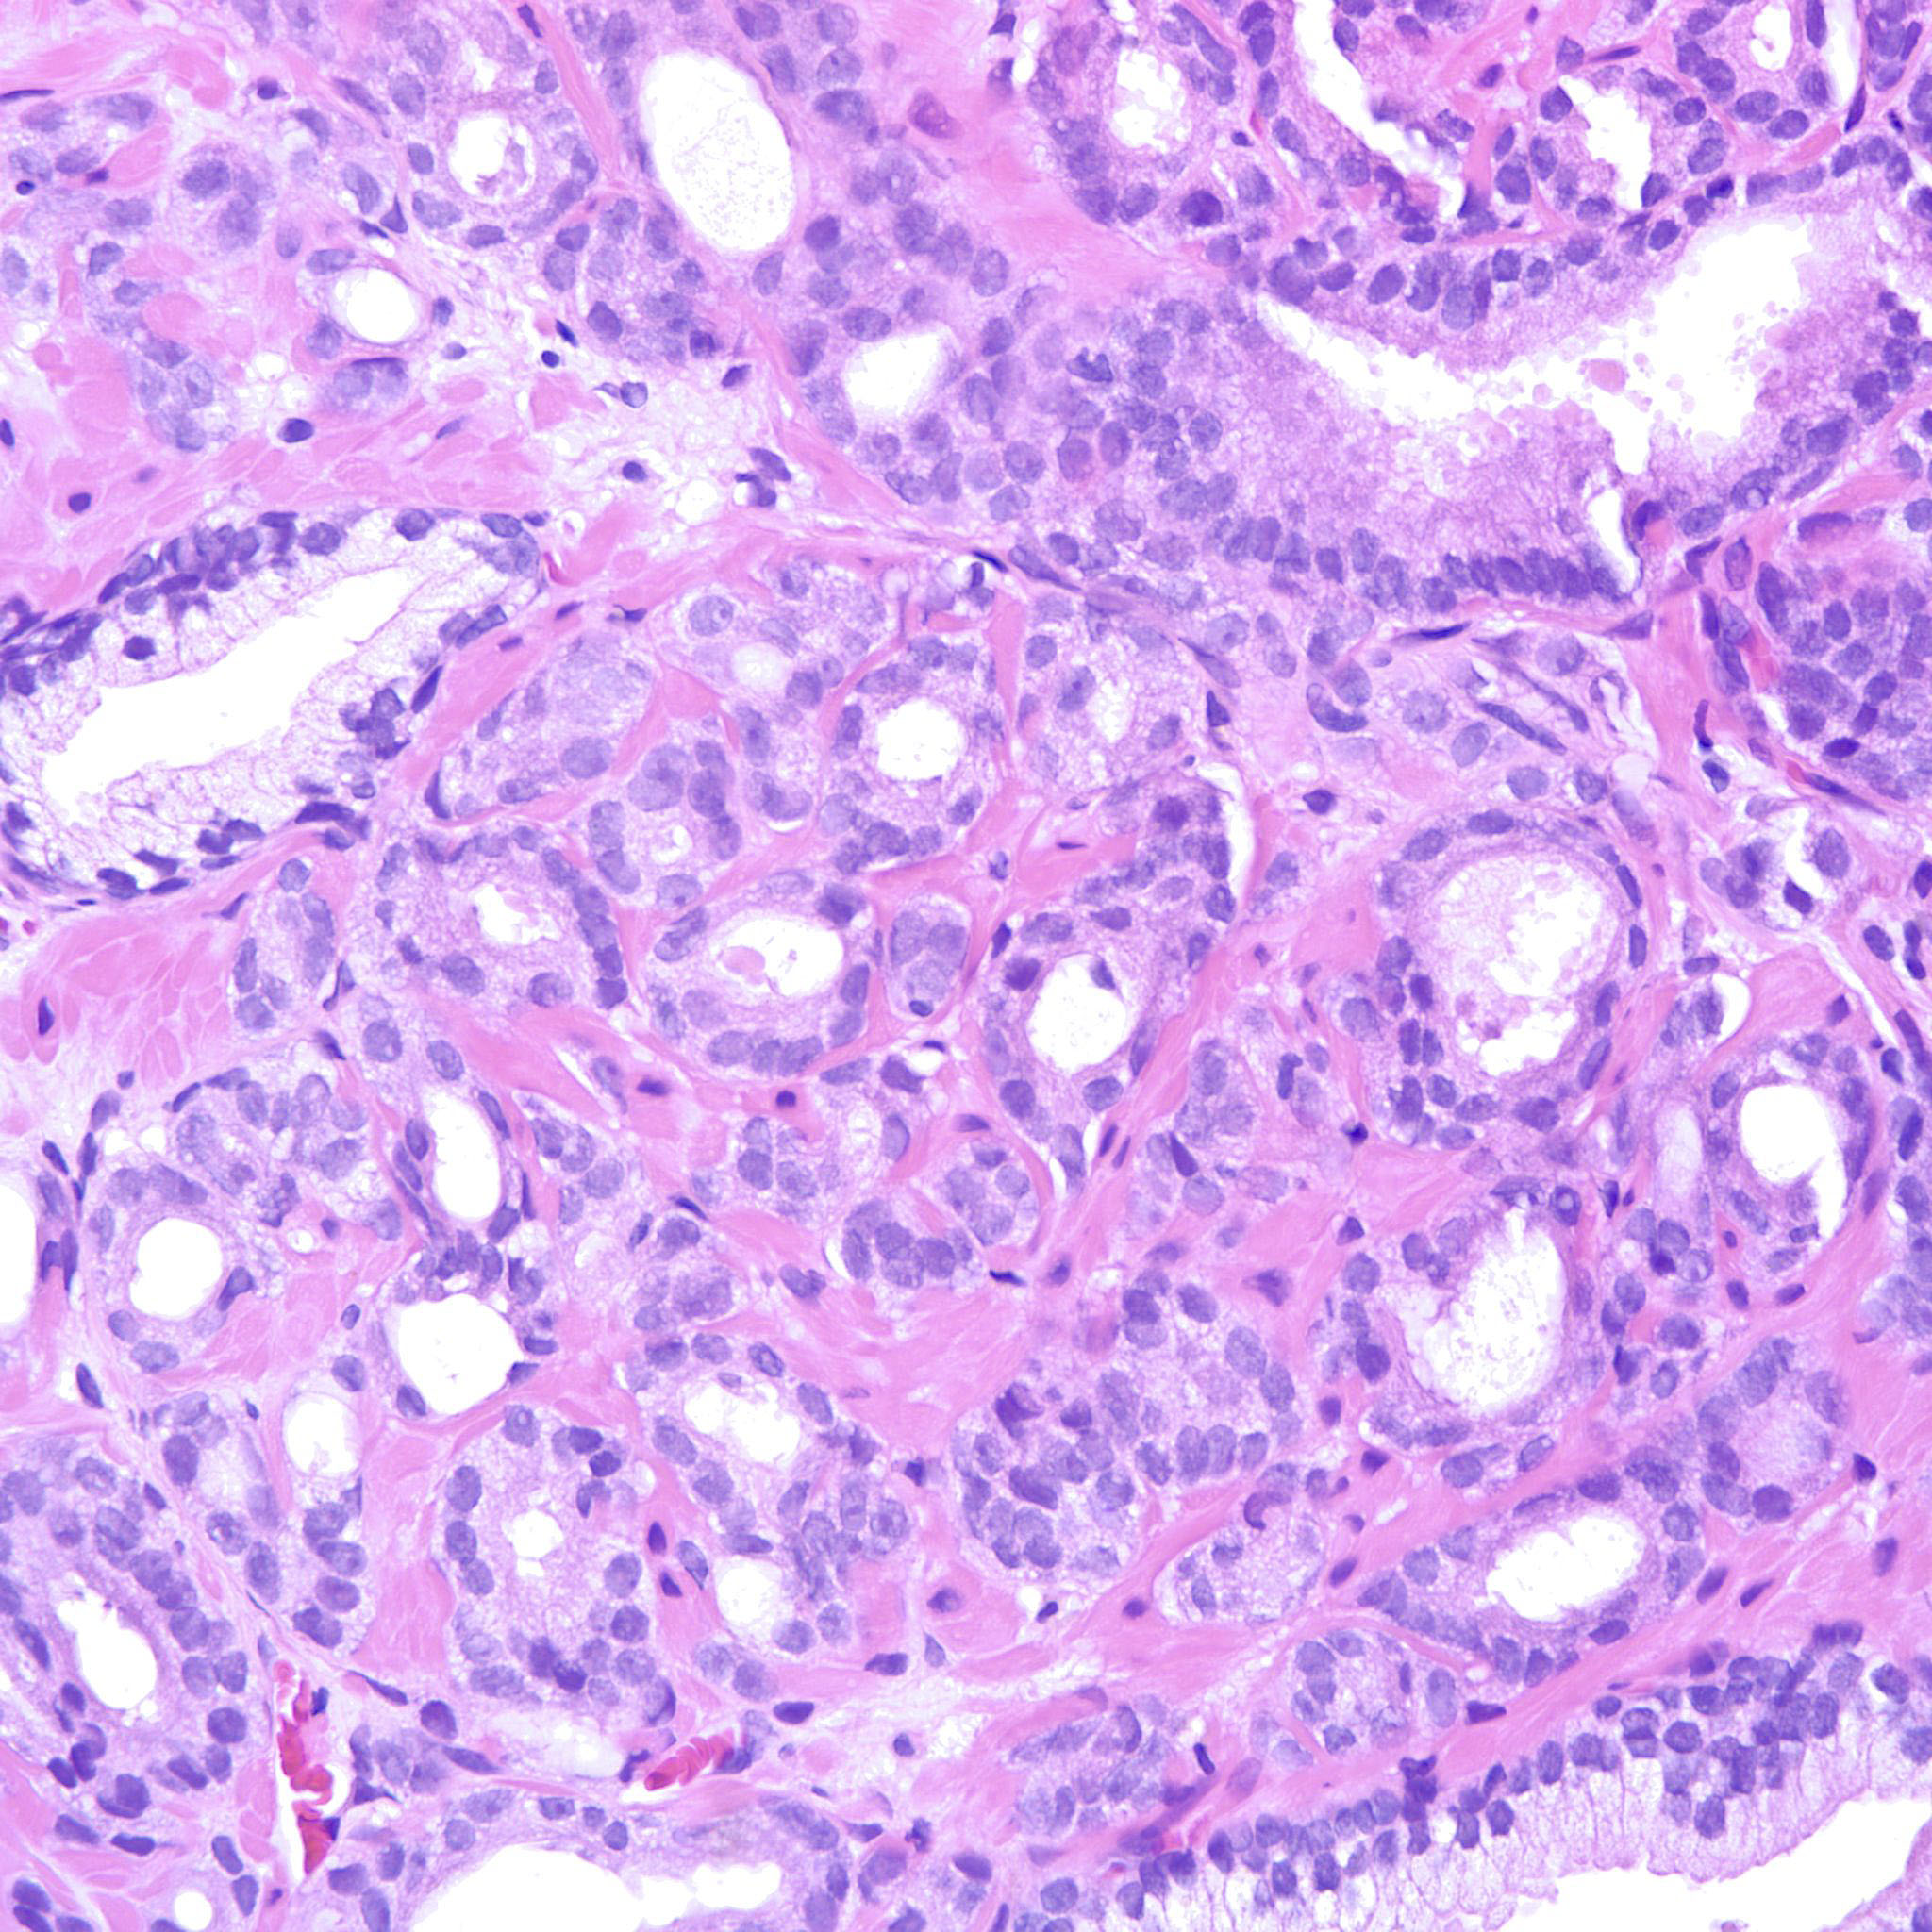

Prostate cancer grading

Case ID: 214